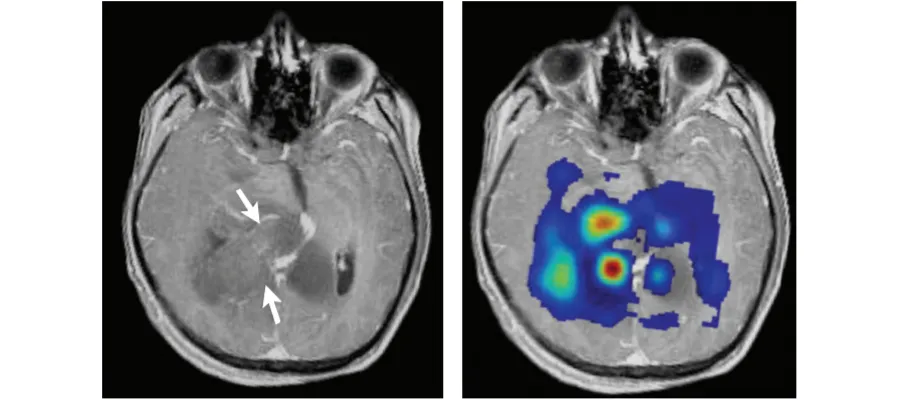

MRI images of glioblastoma (from Kao et al. BioMed Res Int: 970586).

Glioblastoma is an aggressive type of cancer that can occur in the brain or spinal cord and accounts for more than 50% of all primary brain tumours. It can occur at any age, but tends to be more frequent in older adults. People can experience headaches, seizures and weakness. Despite surgery, chemotherapy and radiotherapy, glioblastoma remains an incurable disease.